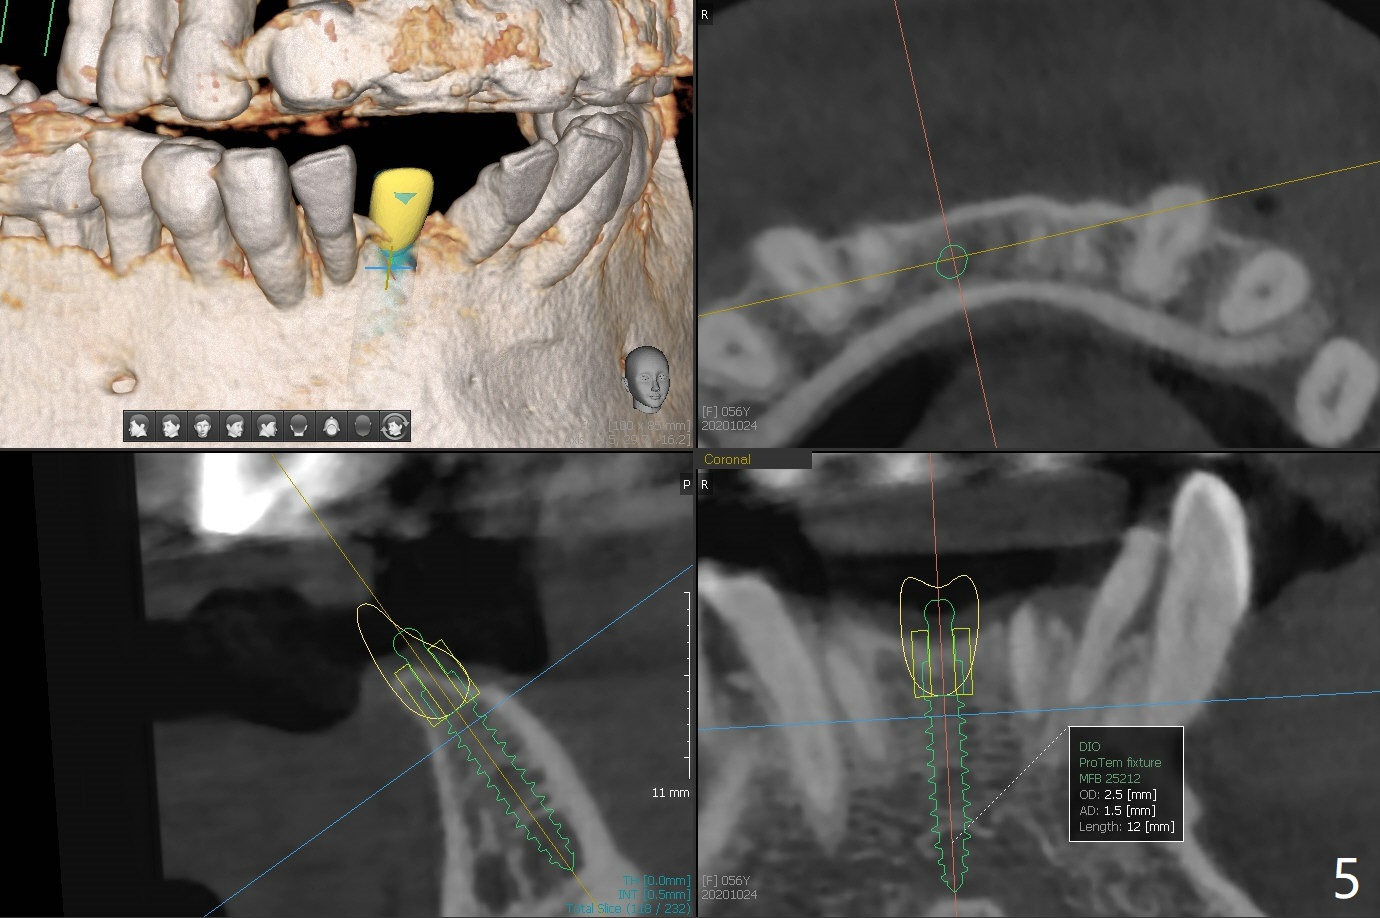

56岁女牙周炎,失去右上6,7以及右下1,后者缺牙间隙特别宽,其余切牙往颊侧移位(flare,病人不愿意拔除,图一)。右上植牙修复后(图二,三),下前牙种植(图四,五(选择窄植体)),建立正常覆盖,同时在邻近切牙唇侧植骨(图七,八:红线)。四-六个月后做局部矫正:使用植牙作为支抗将颊侧移位的前牙(牙冠)往舌侧推移(图七,八:蓝箭头),而牙根可能往唇侧移位(图六:红箭头),所以事先植骨(图七,八:红线)重要。矫正后3-3舌侧放置钢丝树脂固定。Jennifer: #25 implant and crown should be lingualized, as compared to the rest of the lower incisors (flared). After osteointegration, ortho will be conducted to correct the flaring using #25 implant as an anchor.